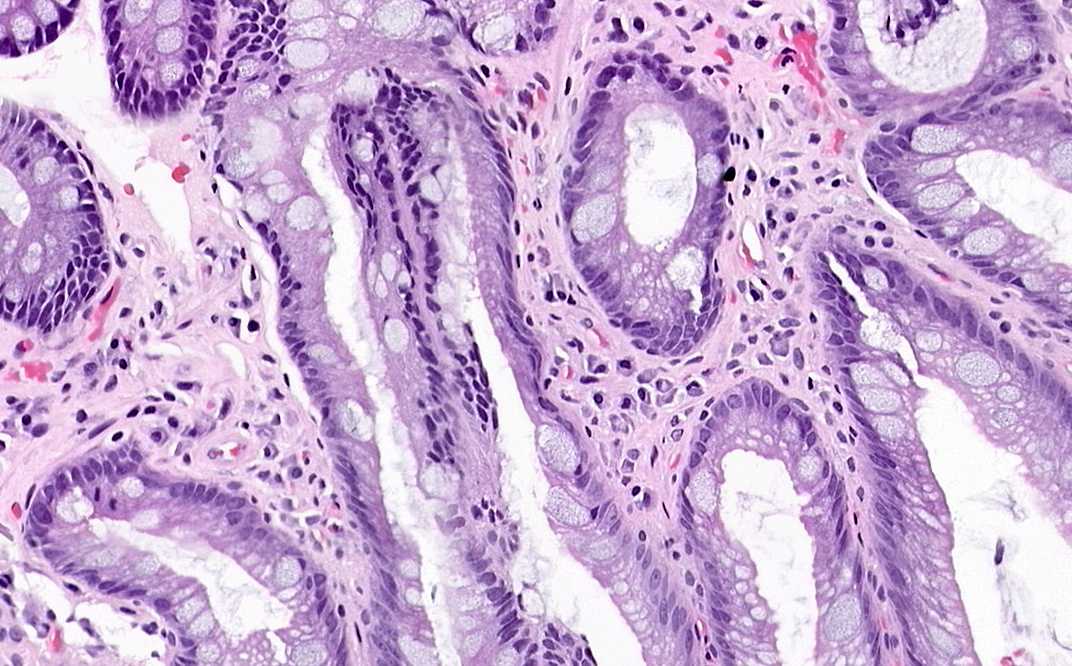

Hematoxylin & eosin

Area 1: The squamous epithelium (S) is histologically different from the columnar epitheliums which has gland formation. On higher magnifications, you can see the goblet cells (arrow) in the specialized columnar metaplastic epithelium.

Area 2: This fragment is composed exclusively composed of specialized metaplastic epithelium. Goblet cells are a lot more common.

• The specimen is an endoscopic biopsy and contains 4 fragments of tissue. In one of the fragments (Area 1), there is both squamous epithelium and columnar epithelium. The squamous epithelium indicated that this is obtained from the esophagus or gastroesophageal (GE) junction. The presence of columnar epithelium, however, does not necessarily mean that the biopsy is obtained at the GE junction because metaplastic columnar epithelium can be found in areas higher than the GE junction. Usually, the endoscopist will specify the location where the biopsy is taken (expressed in cm distal to the incisors).

• There are two types of metaplastic epithelium. The gastric type have histologic features similar to the stomach. The other is the colonic (intestinal) type that contains mucin containing goblet cells. This type is associated with increase risk of malignancy. The metaplastic changes often but not always contain both types. The identification of genuine goblet cells is necessary for a diagnosis of Barrett's esophagus (specialized columnar epithelium). Identification of goblet cells is therefore an important task.